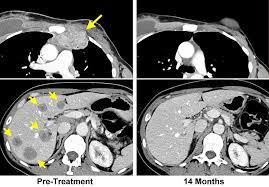

Histone Deacetylase 11 Inhibition Promotes Breast Cancer Metastasis From Lymph Nodes Nature Communications from media.springernature.com Metastasis to the lungs may cause: While it is not curable, metastatic breast cancer can be treatable — especially with the advent of new therapies, including biologic targeted treatments and novel drug combinations. Jaundice, which is a yellowing of the skin and eyes swelling in the abdomen due to a buildup of fluid The liver is a common site for metastases from many cancer types. The most common breast cancer metastasis sites are the bones, the lungs, the brain, and the liver. Symptoms of breast cancer metastasis to liver metastatic breast cancer may grow silently in the body while you are completely unaware. Common symptoms of metastatic liver cancer include: Jaundice (a yellowing of the skin and the whites of the eyes) may occur, as well as abdominal discomfort, nausea, and vomiting.

It's also known as stage 4 breast cancer. Common symptoms of metastatic liver cancer include: Metastatic breast cancer may have cancer travel to the liver, called liver metastases. Sometimes you may feel pain in the right shoulder. Some people may have discomfort around the liver area only, while others may feel pain under their ribs or across their upper abdomen. About half of people diagnosed with. The symptoms of metastatic liver cancer vary depending on where new tumors form. My hilars enlarged ( my first metastatic site) and the fatigue could of been from my persistent cough. In retrospect , i was feeling more tired, sporadic feeling nauseous and a dull pain on my right side under last rib. Bone pain or bone fractures due to tumor cells spreading to the bones or spinal cord Symptoms of breast cancer metastasis to liver metastatic breast cancer may grow silently in the body while you are completely unaware. A doctor is more likely to find the cancer on a liver function test. In later stages, cancer can cause the liver to swell or obstruct the normal flow of blood and bile.